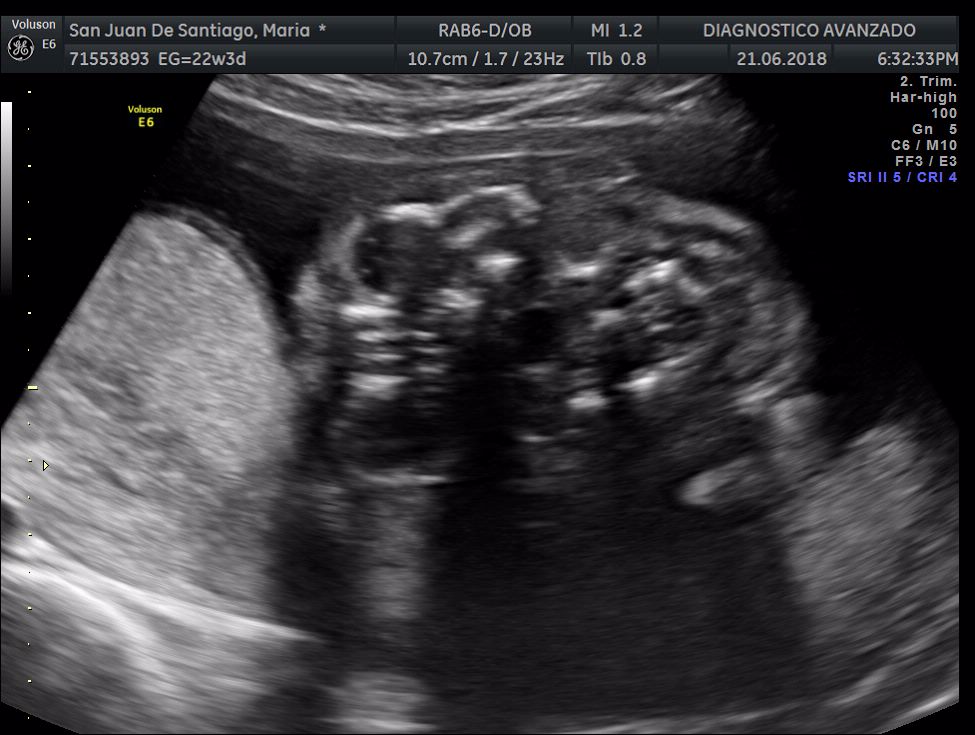

¡Hola a todos! Hoy hemos ido a hacer la tradicional ecografía 3D de la niña, os dejamos todo el material (aunque es un poco demasiado).